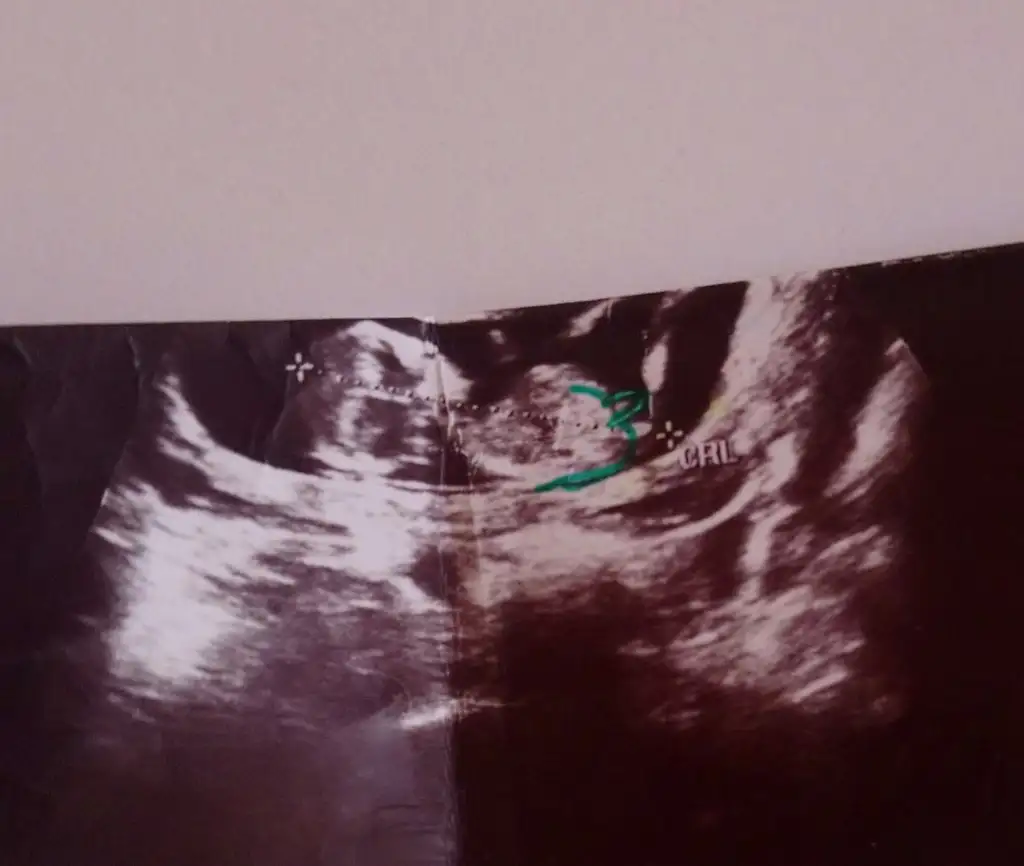

Usg fotosuna nub kısmı çizdim paralel mi kızlar